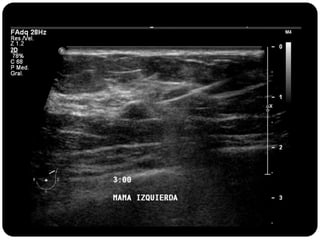

Paciente femenina de 66 años con historia clínica de 1er gesta antes de los 30 años y antecedentes de lactancia positiva, presenta una lesión palpable en la mama derecha. Los estudios radiológicos indican un diagnóstico de bi-rads 5, con biopsias revelando adenocarcinoma lobulillar infiltrante en la glándula mamaria derecha y adenocarcinoma ductal in situ en la izquierda. El caso fue evaluado por las doctoras Jacqueline Preciado Vargas y Beatriz E. González Ulloa.